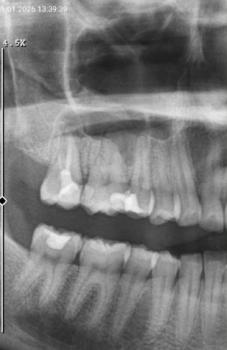

This case shows severe tooth decay affecting the back teeth, with decay extending close to or into the tooth roots. Dark, broken tooth structure is visible, which indicates long-standing dental caries. The surrounding gum tissue appears irritated, increasing the risk of infection.

Treatment starts with a dental examination and X-ray to assess the depth of decay. If the tooth structure is too damaged, tooth extraction is often required. In some cases, root canal treatment may be possible, followed by restoration. Infection control is the priority to prevent further complications.